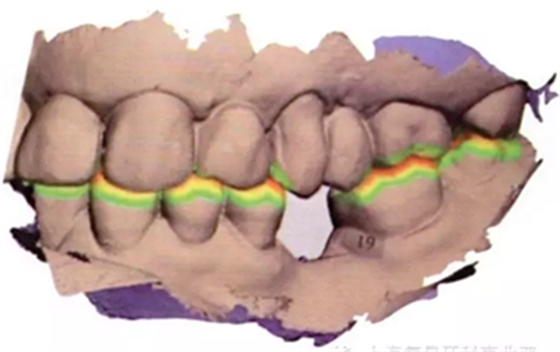

將從CBCT中獲得的數(shù)字掃描文件和DICOM文件導(dǎo)入到Implant Studio軟件中(3Shape),一種新的空間技術(shù)可以創(chuàng)建口腔內(nèi)真實情況的三維重疊圖像和放射圖片。Implant Studio中的修復(fù)性設(shè)計工具可用來在修復(fù)表面圖片上創(chuàng)建一個處于理想修復(fù)位置的符合功能性和美觀性的虛擬牙冠(圖4a-d)。

可使用口腔內(nèi)表面掃描來設(shè)計治療方案,同時可用錐形束來三維重建進行檢查,以確保植入位置最佳,避免發(fā)生任何骨開窗或骨開裂的可能(圖6a-6b)。